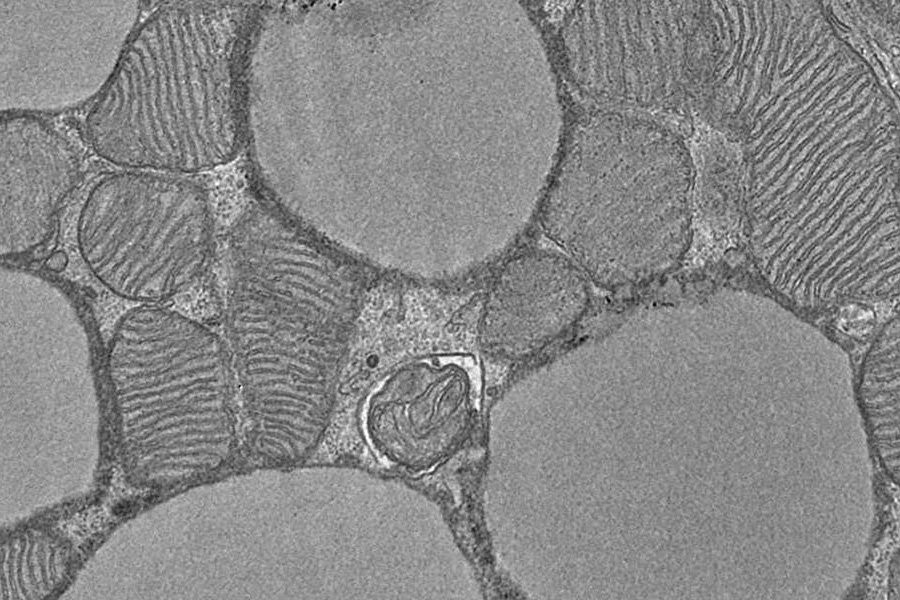

Клетки бурого жира особенно богаты митохондриями, энергетическими станциями , где происходит клеточное дыхание . Однако наука пока недостаточно понимает, как клетки бурого жира усиливают метаболизм, чтобы можно было разработать новые методы лечения.

Эти результаты были получены на изолированных митохондриях, культивируемых клетках и животной модели. «Хотя мы нашли важную часть головоломки для понимания термогенеза, терапевтическое применение еще далеко», — объясняет Хенвер Брунетта, проводивший исследование.